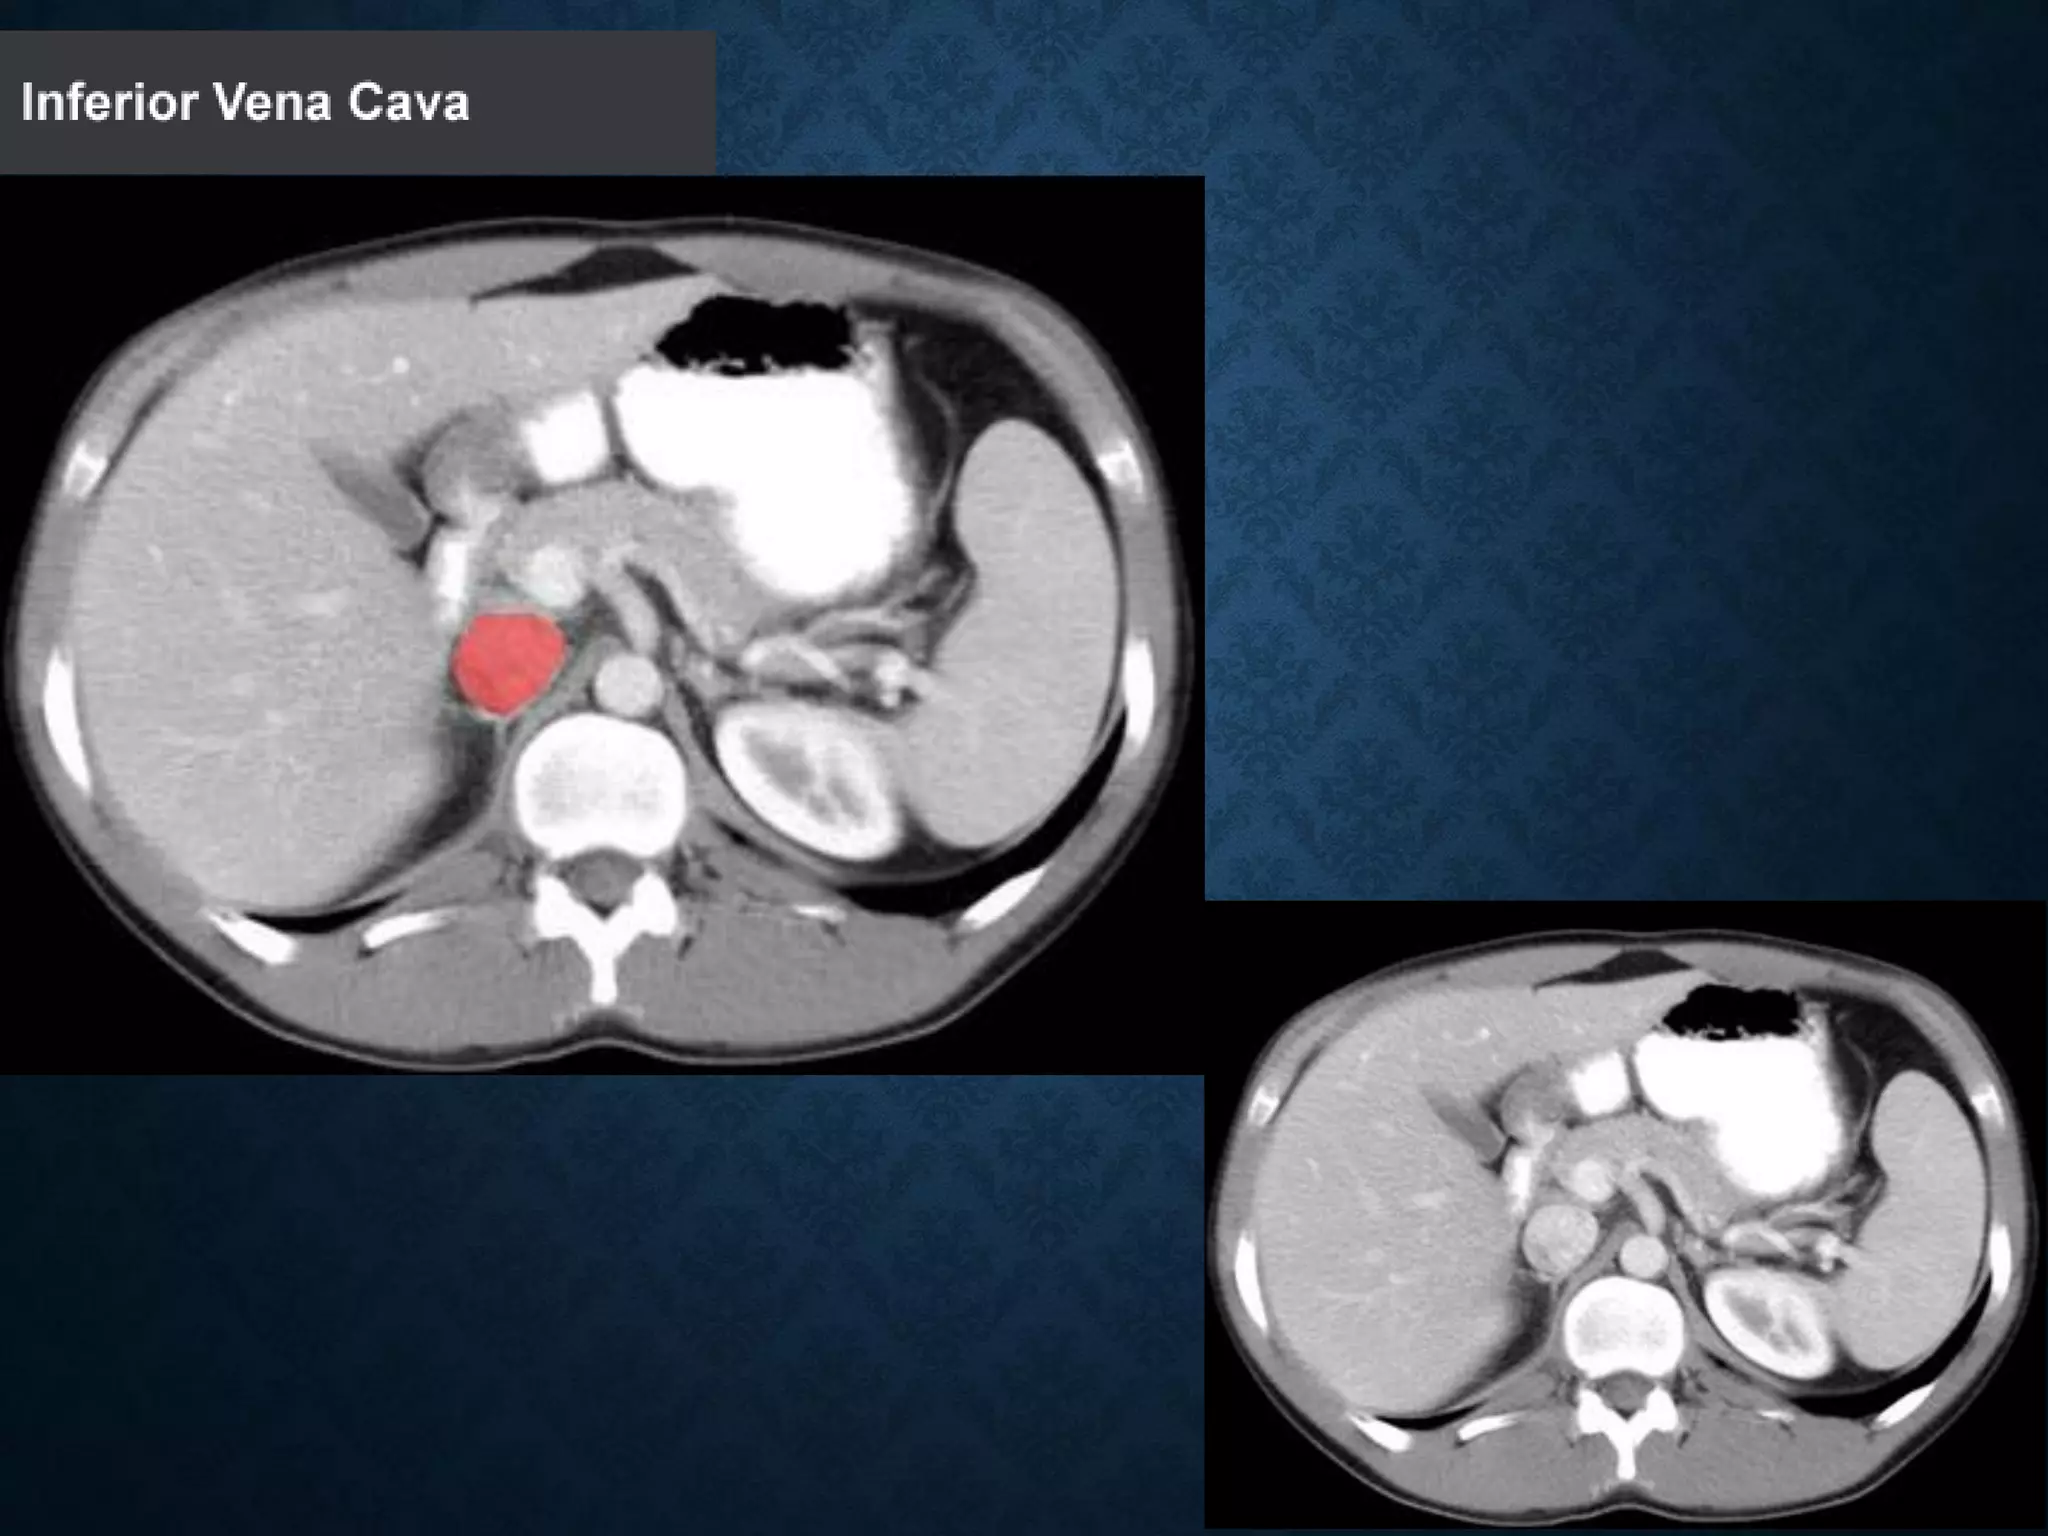

ABDOMINAL AORTA

origin: Continuation of descending thoracic aorta at T12

• course: descends anterior and slightly to the left of the lumbar vertebral

bodies.

•Bifurcation of aorta:L4

• Note that the bifurcation (union) of the inferior vena cava is at L5and

therefore below that of the bifurcation of the aorta)